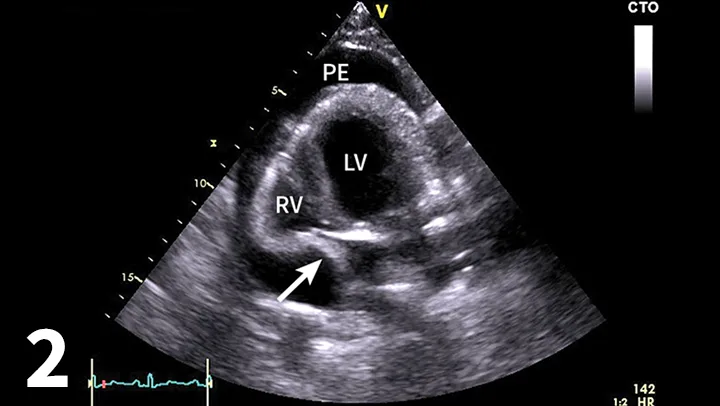

• Echocardiography confirms an echo-free space between the heart and the pericardium (Figure 1), may show cardiac tamponade (Figure 2), and may detect mass lesions.

Figure 2

Four-chamber left apical echocardiographic view showing moderate pericardial effusion with cardiac tamponade. Arrow shows diastolic collapse of the right atrium consistent with cardiac tamponade. (PE = pericardial effusion, LV = left ventricle, RV = right ventricle)

• Evaluate for the presence of cardiac tamponade (eg, diastolic collapse of the right atrium) (Figure 2).